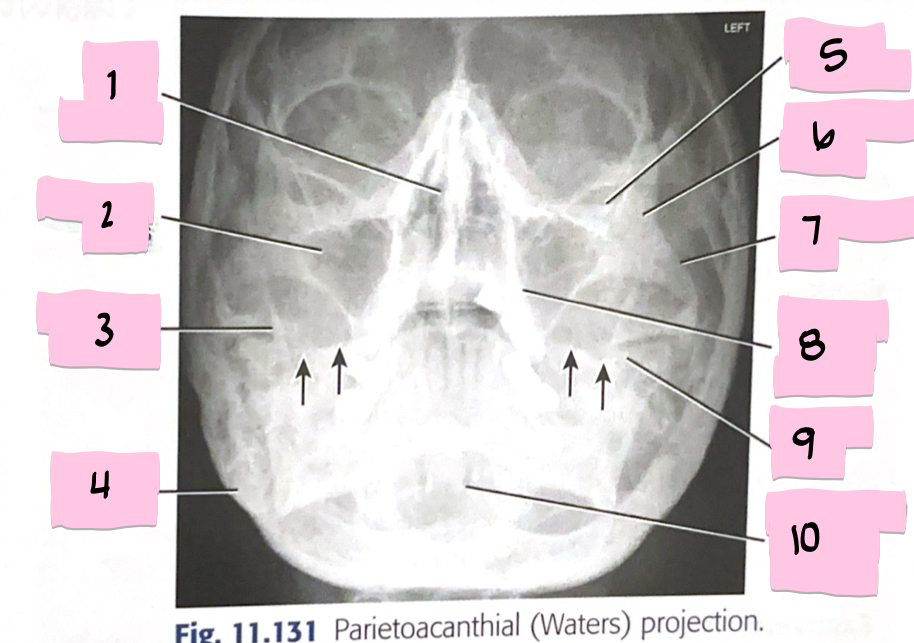

What is 1 pointing to?

Bony nasal septum

What is 2 pointing to?

Maxillary sinus

What is 3 pointing to?

Coronoid process

What is 4 pointing to?

Mastoid process

What is 5 pointing to?

Inferior orbital rim

What is 6 pointing to?

Zygomatic bone

What is 7 pointing to?

Zygomatic arch

What is 8 pointing to?

Maxillary alveolar process

What is 9 pointing to?

Petrous ridge

What is 10 pointing to?

Dens within foramen magnum